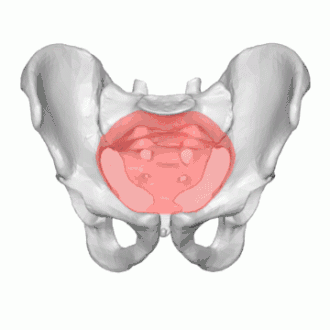

The pelvic inlet or superior aperture of the pelvis is a planar surface which defines the boundary between the pelvic cavity and the abdominal cavity (or, according to some authors, between two parts of the pelvic cavity, called lesser pelvis and greater pelvis). It is a major target of measurements of pelvimetry.

Its position and orientation relative to the skeleton of the pelvis is anatomically defined by its edge, the pelvic brim. The pelvic brim is an approximately apple-shaped line passing through the prominence of the sacrum, the arcuate and pectineal lines, and the upper margin of the pubic symphysis.